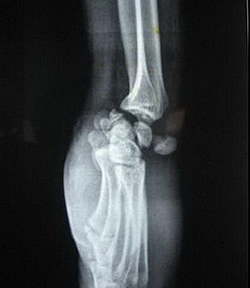

Перилунарные вывихи кисти

Вывихи кисти составляют около 90% всех вывихов. Они возникают при падении с упором на кисть или резком разгибании. При перилунарном вывихе кисти сохраняется контакт между полулунной и лучевой костью, в то время как остальные кости запястья смещаются к тылу и центру. Этот тип вывиха иногда сопровождается переломами трехгранной и ладьевидной костей, а также шиловидных отростков.

Перелом ладьевидной кости всегда сопровождается вывихом. При этом полулунная кость и центральный фрагмент ладьевидной кости сохраняют свое положение. Остальные кости запястья, а также дистальный отломок ладьевидной кости смещаются к тылу.

Чрезладьевидно-чрезполулунные вывихи кисти

Перелом полулунной и ладьевидной костей сопровождается смещением дистальных отломков вместе с остальными костями запястья к тылу и центру, в то время как проксимальные (центральные) отломки остаются на месте.